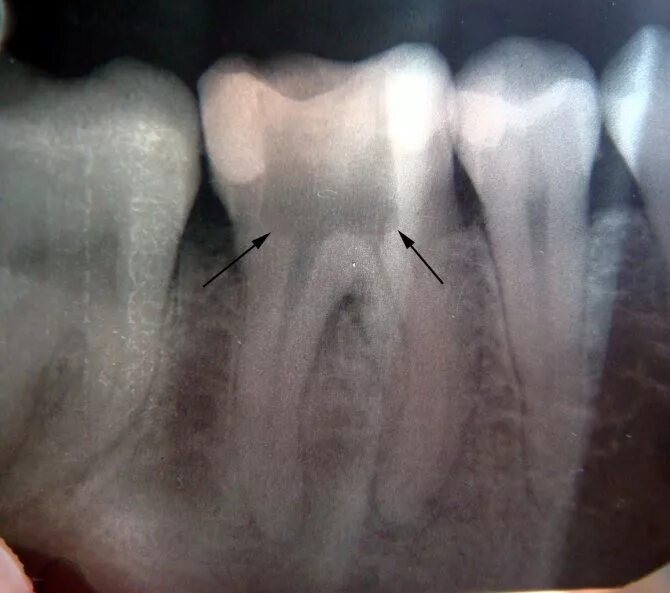

Сообщающаяся с полостью зуба